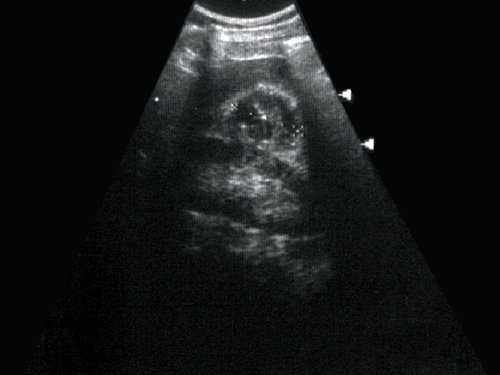

Данные УЗИ: правая почка с четкими неровными контурами, размером 12,5х6,5 см, подвижная при дыхании. Паренхима верхнего сегмента почки толщиной 1,6 см. В нижнем сегменте почки, преимущественно экстраренально определяется округлое образование повышенной эхоструктуры, до 3 см в диаметре. Подвижность почки 2 см.

Левая почка с четкими неровными контурами, размером 11,5х5,5 см. Паренхима однородная, толщиной до 1,7 см. Чашечно-лоханочная система не дилатирована. На границе верхнего и среднего сегментов определяется округлое образование повышенной эхогенности, 1,7 см в диаметре. Подвижность почки - до 2 см (рис. 1).

Рис. 1. Ультрасонограмма - стрелкой указано округлое образование в нижнем сегменте почки.